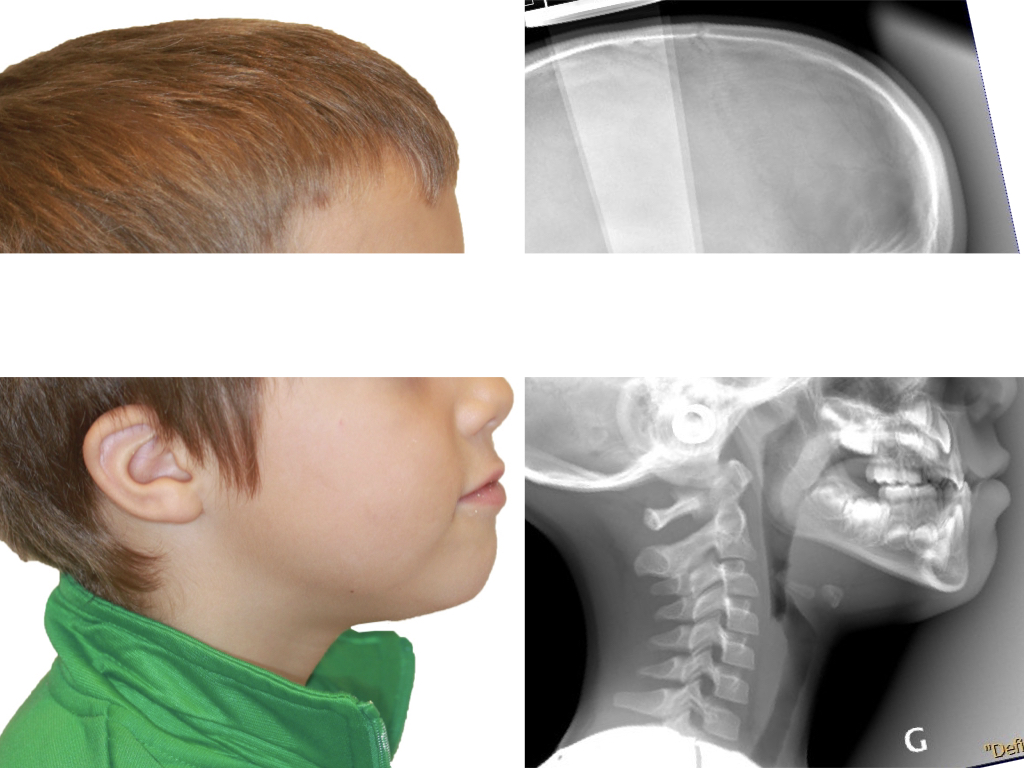

NUUMOON En images Arrêt des parafonctions (lolette, pouces, etc…) Orthodontie pédiatrique Orthopédie dento-faciale Apnée du sommeil de l’enfant (TROS) Esthétique du sourire Orthodontie et Articulation Temporo Mandibulaire (ATM) Traitement combiné ortho-chirurgicaux Traitements pluridisciplinaires Arrêt des parafonctions Effet de la lolette sur les dents Effet du pouce sur les dents Position de la langue et impact sur les dents Mieux respirer pour mieux grandir Respiration et santé Respiration et santé Sans titre.004 Orthodontie pédiatrique Conséquences ventilation orale – nuumoon ChatGPT Image 5 sept. 2025, 09_00_25 conséquences posturales de la ventilation orale Prévention canine incluse Prévention canine incluse Prévention canine incluse Dents qui s’emboitent à l’envers Dents qui s’emboitent à l’envers orthopédie dento-faciale Traitement déformation mâchoire Déformation des mâchoires : menton en avant Déformation des mâchoires : menton en avant Déformation machoire Déformation machoire Déformation machoire : machoire du bas en arrière Déformation des mâchoires : menton en avant Déformation des mâchoires : menton en avant Posture dents et mâchoire Anomalie de la mâchoire Apnée du sommeil orthodontie invisible à Genève Aligneurs transparents & bagues linguales – l’art de corriger sans rien laisser paraître Troubles de l’articulation temporo-mandibulaire et bruxisme Chirurgie orthognathique Traitements pluridisciplinaires INSIGHTS Contenu pour les enfants